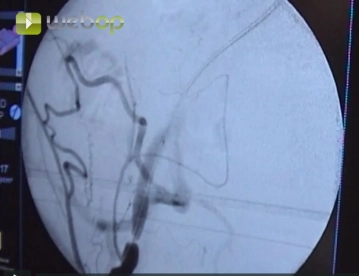

Instilação de solução salina-heparina de 2000 UI centralmente e inserção de um fio Terumo® na aorta terminal. DSA retrógrada da estenose da artéria ilíaca externa usando técnica de roadmapping.

Roadmapping (“Pathfinder”):

Neste processo, um pequeno bolus de meio de contraste é aplicado para exibir a aorta abdominal como um roadmap (“mapa de rua”). Esta imagem é armazenada como uma máscara. As imagens subsequentes são então tiradas sem meio de contraste e subtraídas da máscara. Dessa forma, por exemplo, apenas um cateter radiopaco com sua posição atual pode ser exibido. Nas imagens de subtração criadas dessa forma, o cateter brilhante é visível sobre a aorta abdominal escura, e o fundo irrelevante para este exame é apagado.